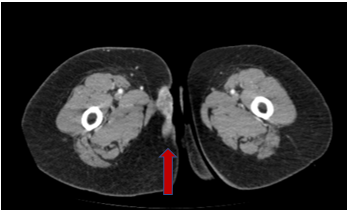

Se intervino en mayo del 2021 realizando exéresis del implante de 4x2,5 cm con márgenes libres. La anatomía patológica confirmó el hecho de ser una metástasis (fig.1) y no un primario ya que no había afectación de epidermis (fig.2, fig.3), el tumor crecía desde las capas inferiores a las superiores.

Fig. 1 Metástasis cutánea de carcinoma anal

Fig. 2 TAC abdomino-pélvico con cortes bajos donde se evidencia el implante (flecha roja)